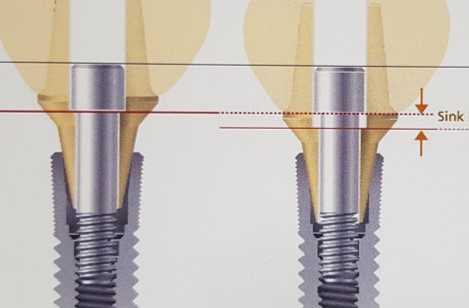

2) Sinking(sink down, 침하)

Sink down

Sink down